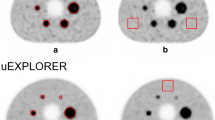

Clinical Evaluation

The reconstructed PET/CT and PET/MRI datasets were qualitatively evaluated. A set of anatomical landmarks were scored for each patient and acquisition time. Table 1 and supplementary Tables 2 to 4 summarize these results, averaged over all patients. Table 1 shows the overall image quality scores (see sample brain and whole-body images in Figs. 6 and 7, respectively), both for brain and whole-body studies. PET/MRI and PET/CT scores are provided in pairs, in decreasing acquisition time steps. The corresponding tables for the image sharpness (Suppl. Table 2), artifacts (Suppl. Table 3), and noise (Suppl. Table 4) are provided as Supplementary Material. There was a statistically significant difference for body imaging in image quality (p < 0.001), image sharpness (p < 0.001), and noise (p < 0.001) while there was no significant difference for artifacts (p > 0.05), showing a superiority of PET/MRI versus PET/CT. Remarkably it can be noticed that the differences in body imaging can be seen in all categories and at all time point, except in artifacts.

However, no significant difference was noticed in brain imaging where both imaging methods showed comparable results (p > 0.05) (Figs. 2, 3, 4, and 5).

In this study, we assessed the PET performance of both PET/CT and PET/MRI scanners for five brain and five whole-body studies. The PET/MRI acquisition time was retrospectively adjusted for each patient to account for tracer decay since the start of the PET/CT acquisition. This ensured that the reconstructed images used for the evaluation offered a fair comparison where both systems had been exposed to equivalent amounts of the emitted signal (Figs. 6 and 7).

Clinical evaluation shows equivalent performance for brain studies. This is coherent with literature [9, 15]. Most of the FOV of PET/MRI is not used, so sensitivity cannot be taken advantage of and lead to improved image quality. This is due to the fact that the slice-wise increase of sensitivity at the isocenter is not large enough to make a noticeable difference in brain images. Another reason for this observation could be that the image quality in brain PET/CT images is already very good and that improvements due to increased counts are hard to distinguish.

The image quality, sharpness, artifacts, and noise for PET/CT and PET/MRI for all acquisition times were clinically assessed and scored.